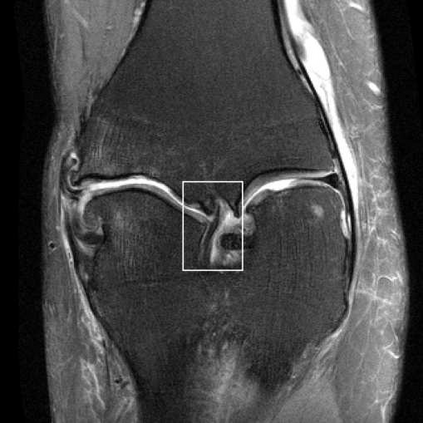

Deep Learning (DL) methods have shown promising results for solving ill-posed inverse problems such as MR image reconstruction from undersampled $k$-space data. However, these approaches currently have no guarantees for reconstruction quality and the reliability of such algorithms is only poorly understood. Adversarial attacks offer a valuable tool to understand possible failure modes and worst case performance of DL-based reconstruction algorithms. In this paper we describe adversarial attacks on multi-coil $k$-space measurements and evaluate them on the recently proposed E2E-VarNet and a simpler UNet-based model. In contrast to prior work, the attacks are targeted to specifically alter diagnostically relevant regions. Using two realistic attack models (adversarial $k$-space noise and adversarial rotations) we are able to show that current state-of-the-art DL-based reconstruction algorithms are indeed sensitive to such perturbations to a degree where relevant diagnostic information may be lost. Surprisingly, in our experiments the UNet and the more sophisticated E2E-VarNet were similarly sensitive to such attacks. Our findings add further to the evidence that caution must be exercised as DL-based methods move closer to clinical practice.